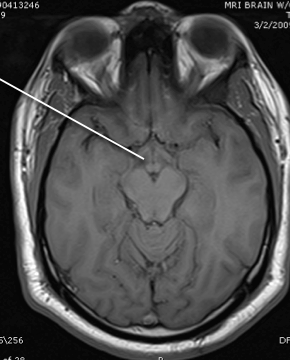

crus cereberi

hypothalamus

cerebral aqueduct

cerebellum